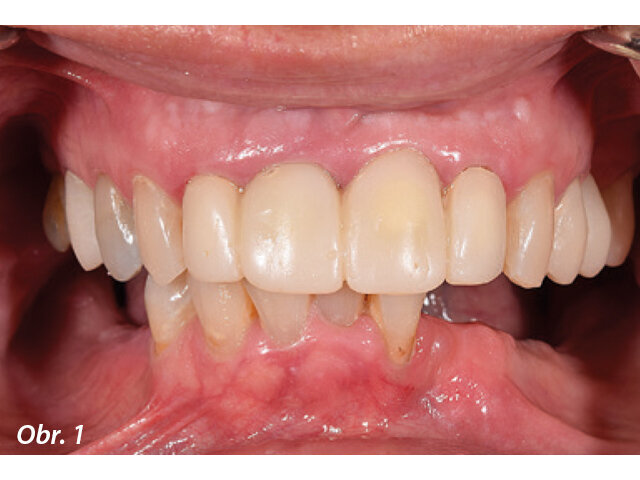

Pacientka si zvolila komplexní rehabilitaci chrupu v dolní čelisti fixní náhradou nesenou implantáty s využitím čtyř implantátů. Zbývajících pět zubů vykazovalo vhodný vertikální rozměr okluze v centrickém vztahu s okluzní rovinou poskytující přijatelnou fonetiku a estetiku (obr. 1). Byl pořízen panoramatický rentgenový snímek pro zaznamenání dentoalveolárního stavu v době, kdy se pacientka dostavila poprvé do ordinace (obr. 2). Předchozí selhávající distální fixní zubní náhrada byla odstraněna ještě před definitivním plánováním léčby.

Obr. 2: Panoramatický rentgenový snímek demonstrující počáteční dentoalveolární stav